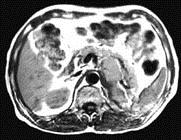

问题 女,34岁,无意中发现血压升高4 个月就诊,行CT检查,如图所示,下列说法正确的是 ( )

选项 A、考虑为左肾上腺嗜铬细胞瘤 B、考虑为左肾上腺转移瘤 C、增强扫描,该病灶周边明显强化,中心处强化不明显 D、考虑为左肾上腺腺瘤 E、CT示左侧肾上腺区可见一等密度块影,边界清楚

答案 ACE